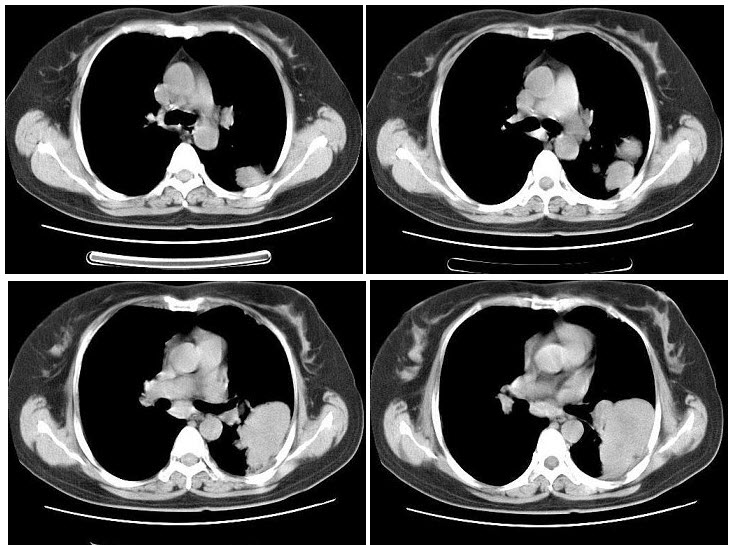

6、多项选择题

男,45岁,间断性腰背痛4个月,突发左下肢全肢水肿,小腿有张力性水泡,胸腹部CT扫描如图,下列哪些征象或结论正确()

A.下腔静脉缺如

B.下腔静脉变细

C.奇静脉增粗

D.奇静脉变细

E.正常CT表现